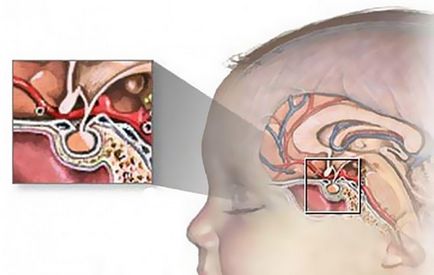

Este imposibil să se supraestimeze importanța funcționării normale a texturii trunchiului. Este suficient să rețineți că în trunchi există centre nervoase care reglează activitatea cardiacă și normalizează respirația.

Tulpina creierului participă la mișcarea ochilor, la expresiile faciale, la înghițire, la vorbire și la auz.

Fibrele nervoase trec prin tulpina creierului, care inervază mușchii corpului și membrelor. Prin urmare, cu daune stem, se manifestă mii de semne.